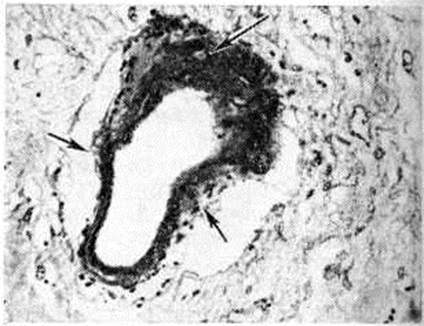

Геморрагический инсульт, как правило, возникает при заболеваниях, протекающих с повышенным артериальное давление. Это обусловлено тем, что сосудистые кризы (смотри полный свод знаний), характерные для гипертонической болезни (смотри полный свод знаний) и артериальной гипертензии (смотри полный свод знаний Гипертензия артериальная), приводят к морфологический изменениям стенок внутримозговых сосудов с нарушением их проницаемости — плазматическому пропитыванию (рисунок 1), некрозам (рисунок 2), образованию микроаневризм (рисунок 3) и их разрывам. Разрыв врождённых артериальных и артериовенозных аневризм может протекать на фоне нормального давления. Преимущественная локализация и характер геморрагий определяются особенностями ангиоархитектоники различных отделов мозга. При гипертонической болезни наиболее тяжёлым изменениям подвергаются сосуды подкорковых узлов и зрительного бугра. Это объясняется отхождением глубоких ветвей под прямым углом от средней мозговой артерии, являющейся продолжением внутренней сонной артерии, и незначительным числом анастомозов сосудов в этой области. В связи с этим на вскрытии кровоизлияния наиболее часто (40%) обнаруживаются в подкорковых узлах с распространением в прилежащее белое вещество (так называемый латеральные кровоизлияния, то есть расположенные латерально от внутренней капсулы, рисунок 4). Второе место по частоте (16%) занимают обширные кровоизлияния, разрушающие подкорковые узлы, внутреннюю капсулу, зрительный бугор (так называемый смешанные кровоизлияния — рисунок 5). Кровоизлияния в зрительный бугор (так называемый медиальные — рисунок 6) составляют 10%, в мозжечок — 6—10%, в мост мозга — 5% от общего числа внутримозговых геморрагий. Кровоизлияния только в белое вещество полушарий мозга встречаются крайне редко. Подразделение полушарных кровоизлияний на латеральные, медиальные и смешанные имеет особое значение в связи с хирургическим лечением геморрагического Инсульт.

Кровоизлияния типа гематомы сопровождаются образованием полости, содержащей жидкую кровь или свёртки крови; они составляют 85% внутримозговых кровоизлияний, наиболее часто развиваются в подкорковых узлах, реже в мозжечке. Основной механизм развития гематомы — разрыв патологически изменённого сосуда (рисунок 7). Формирование гематомы идёт путём раздвигания кровью вещества мозга с перемещением его участков, что возможно благодаря резервным пространствам (желудочки, подпаутинное пространство). Размеры гематомы при этом превышают объем разрушенного кровью вещества, сдавление окружающих отделов незначительно; лишь при кровоизлиянии в мозжечок сдавление вещества мозга весьма существенно в связи с анатомическими особенностями задней черепной ямки (рисунок 8).

Кровоизлияния типа геморрагического пропитывания возникают преимущественно в зрительных буграх, реже в мосту мозга и составляют 15% внутримозговых кровоизлияний. Они являются результатом слияния мелких очагов кровоизлияний, возникающих путём диапедеза из мелких сосудов, имеют вид очагов красного цвета, дряблой консистенции и в силу внешнего сходства иногда напоминают геморрагический инфаркт. В первые часы Инсульт нарушается проницаемость сосудов на границе с кровоизлиянием, развивается отёк; кровь распространяется по ходу нервных волокон. К концу первых суток наблюдаются лейкостазы и лейкодиапедез, размеры очага увеличиваются за счёт диапедезных геморрагий и некробиотических изменений в отёчном веществе мозга. Через двое суток начинается процесс репарации — появление зернистых шаров и гипертрофированных астроцитов; позже образуется вал из астроглии и новообразованных сосудов, кровь подвергается гемолизу, появляются макрофаги с гемосидерином, образуются аргирофильные и коллагеновые волокна. Исходом кровоизлияния может быть формирование глиомезодермального рубца или кисты, содержащих гемосидерин (рисунок 9). В 80—85% кровоизлияний на вскрытии выявляется прорыв крови в желудочки, значительно реже — в подпаутинное пространство. В последнее кровь может также проникнуть из четвёртого желудочка. Первичные вентрикулярные геморрагии нетравматического генеза — явление казуистическое. При разрыве врождённых аневризм артерий основания мозга возникают первичные субарахноидальные кровоизлияния, которые обычно локализуются на базальной поверхности или в латеральной борозде; иногда кровь проникает в субдуральное пространство; часто повреждается вещество мозга (субарахноидально-паренхиматозные кровоизлияния). Расположение гематом, образующихся при этом, зависит от локализации аневризмы, обычно это базальный отдел лобной доли или височная область. В части случаев при незначительном субарахноидально-паренхиматозном кровоизлиянии возможен массивный прорыв крови в желудочки (рисунок 10), что иногда ошибочно диагностируется как первичное вентрикулярное кровоизлияние.